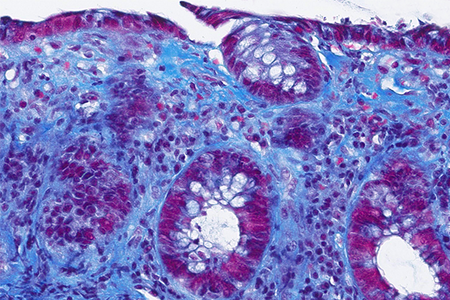

Histology of several colonic sites showed a thickened subepithelial collagen band (>10 μm), predominantly beneath the superficial epithelium but also surrounding the crypts (Panel A). Surface epithelial injury was also observed, with focal mucin depletion and detachment of superficial epithelial cells (Panel B). Lamina propria showed increased cellularity, with lymphocytic and plasmocytic infiltration, along with numerous giant cells (Panel C). There was no crypt architectural distortion. The collagen deposition was highlighted by Masson’s trichrome stain (Panel D) and strongly by tenascin immunohistochemistry (Panel E).

Histological variants of both collagenous and lymphocytic colitis have been described, including collagenous colitis with giant cells. In this variant, multinucleated giant cells are abundant and scattered throughout the lamina propria, with no apparent prognostic value.